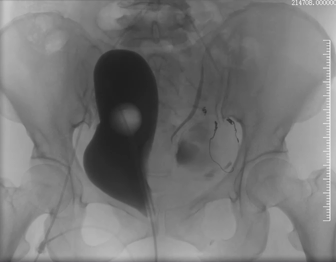

患者因外伤来诊时,CT检查提示骨盆骨折伴盆腔血肿,同时意外发现Stanford B型主动脉夹层——这是两个都可能危及生命的急症。面对如此复杂情况,介入科团队第一时间行动。

在患者生命体征尚平稳但潜在风险极高的情况下,我们结合CT增强检查及三维重建结果,考虑盆腔存在活动性出血,果断通过绿色通道经股动脉穿刺行盆腔动脉造影,竟发现至少3条动脉存在损伤情况。随即迅速以导丝导管结合技术超选择插管至出血责任动脉并成功实施栓塞术。相对传统开腹探查手术,这项微创介入技术不仅大大节省了宝贵的抢救时间,更是避免了开腹手术的创伤,用最小的代价稳定了患者的生命体征,为后续治疗赢得了宝贵时间。